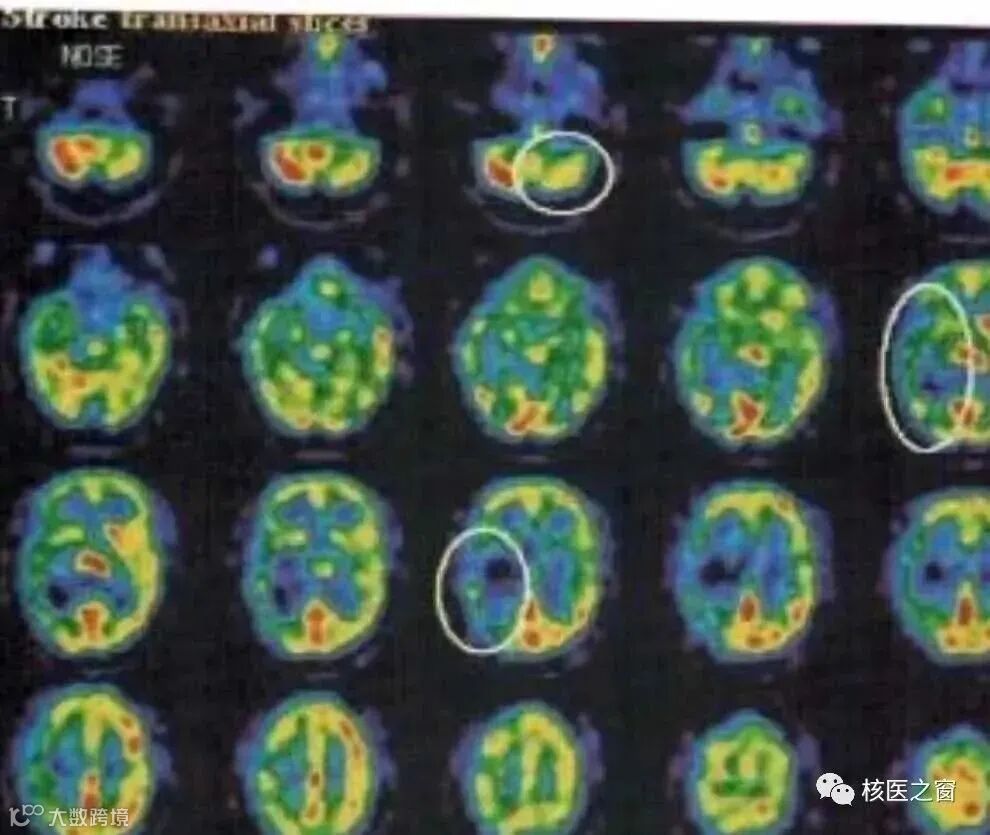

脑血流灌注显像

1.缺血性脑血管病的诊断、血流灌注和功能受损范围的评价;

2.脑梗死的诊断;

3.癫痫致病病灶的定位诊断;

4.评价颅脑损伤后或其手术后脑血流灌注与功能;

5.痴呆的诊断与鉴别诊断;

6.评价脑肿瘤的灌注情况;

7.诊断脑死亡;

8.动静脉畸形的辅助诊断;

9.帕金森病的诊断;

10.情绪障碍(包括焦虑症、恐惧症等)功能损伤的定位与辅助诊断;

11.其他,如偏头痛、抽动症等功能损伤的定位、治疗方法筛选与疗效评价;